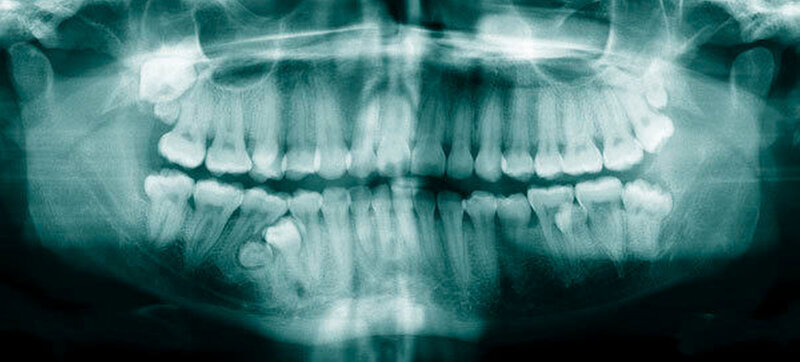

Die Prävalenz überzähliger Zähne wird im Bereich von 0,07 Prozent bis 0,6 Prozent für das Milchgebiss [Luten, 1967; Ravn, 1971; Järvinen Lehtinen, 1981; Magnússon 1984; Skrinjari Barac-Furtinovi, 1991; Yonezu et al., 1997; Chen et al., 2010] und von 0,3 Prozent bis 3,2 Prozent für die bleibenden Zähne [Luten, 1967; Bäckman Wahlin, 2001; Salcido-García et al., 2004; Leco Berrocal et al., 2007; Gündüz et al., 2008; Yagüe-García et al., 2009; Schmuckli et al., 2010; Fardi et al., 2011] angegeben. Die Mehrheit der überzähligen Zähne im Milchgebiss sind seitliche Schneidezähne im Oberkiefer, die meist mit einer normalen Morphologie und Lage durchbrechen (Abbildungen 1 bis 3) [Luten, 1967; Humerfeld et al., 1985; Garvey et al., 1999; Ferrés-Padró et al., 2009]. Der oft ungestörte Durchbruch und das Ausbleiben von Symptomen führen dazu, dass überzählige Zähne in der Milchdentition oft gar nicht diagnostiziert werden, und dies wird auch als Erklärung für die unterschiedlichen Prävalenzen überzähliger Zähne im Milch- und bleibendem Gebiss angeführt [Wang Fan, 2011]. Überzählige Zähne sind häufiger bei Männern als bei Frauen, wobei über ein Verhältnis von 1,18:1 bis 4,5:1 berichtet wird [Rajab Hamdan, 2002; Fernández Montenegro et al., 2006; Gündüz et al., 2008; Wang Fan, 2011]. In der Schweiz publizierten von Arx (1990) und Schmuckli und Mitarbeiter (2010) Geschlechterverhältnisse von 2,6:1, beziehungsweise 2,75:1. In einer aktuellen Arbeit von Mossaz und Mitarbeiter (2014) von Patienten aus dem Raum Bern lag dieses Verhältnis etwas ausgeglichener bei 1,61 zu 1.

Überzählige Zähne sind die häufigste Ursache für einen unterbliebenen oder verzögerten Durchbruch der oberen Schneidezähne (Abbildungen 13, 14, 15) [Betts Camilleri, 1999]. Besonders beim höckerförmigen Typ kommt es häufig zu Störungen der Eruption der oberen Schneidezähne [Mason et al., 2000]. Diese Komplikation macht sich klinisch initial dadurch bemerkbar, dass die oberen seitlichen Schneidezähne durchbrechen und die Eruption von einem oder beiden zentralen Schneidezähnen ausbleibt [Rajab Hamdan, 2002]. Auch in anderen Lokalisationen der Kiefer können überzählige Zähne zu Durchbruchsstörungen benachbarter Zähne führen [Garvey et al., 1999; Rajab Hamdan, 2002; Mossaz et al., 2014]. Insgesamt liegt die Prävalenz für den Ausfall des Durchbruchs bleibender Zähne bedingt durch überzählige Zähne zwischen 10,2 Prozent und 61 Prozent [Tay et al., 1984; Koch et al., 1986; Tyrologou et al., 2005; Fernández Montenegro et al., 2006; Liu et al., 2007; Gündüz et al., 2008; Hyun et al., 2009; Mínguez-Martinez et al., 2012; Mossaz et al., 2014].